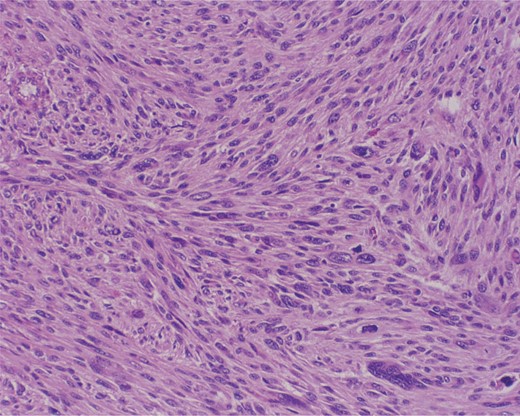

The excisional biopsy was performed in June 2012, which revealed a diagnosis of leiomyosarcoma (slides seen in Figs. 3–5).

Immunostain with SMA (smooth muscle actin). Positive cytoplasmic staining indicating smooth muscle origin.